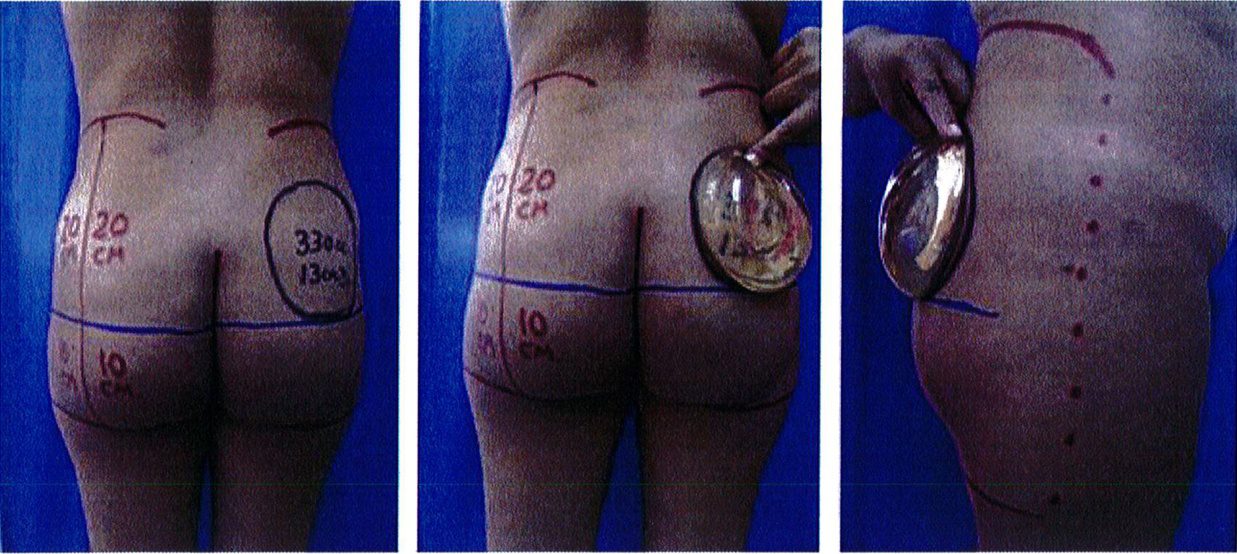

Để tránh tình trạng quá ngắn hoặc quá dài của vùng mông (hay còn gọi là mông dài/ngắn) thì tác giả đã kết hợp một phép đo đơn giản trước phẫu thuật, đo khoảng cách từ mào chậu phía sau tới đường ngang đi qua trung điểm nếp liên mông (khoảng cách A) và từ đường ngang đó tới nếp lằn mông (khoảng cách B) (Hình 1) đế tính vị trí chuẩn xác của khối im- plant.

Để tránh tình trạng phần mông trên được nâng lên quá mức, khoảng cách A thông thường phải gấp đôi khoảng B để có thể phù hợp cho nâng mông dưới cơ.

Nếu khoảng cách A ngắn hơn, nên sử dụng mặt phẳng trong cơ để tạo điều kiện cho khối im- plant được đẩy xuống thấp hơn 1 chút, giúp đạt được kết quả thẩm mỹ lý tưởng.

Những bệnh nhân có mào chậu rộng, khung chậu hẹp và ngắn hoặc sa hay thiếu mô mềm ở mông sẽ không phù hợp với các thủ thuật nâng mông, bất kể áp dụng ở mặt phẳng nào. Các tác giả khuyến cáo họ nên chuyển sang phương pháp ghép mỡ (Hình 2).

Hình. 1. Đánh giá trước phẫu thuật để lựa chọn bệnh nhân với mặt phẳng im- plant phù hợp.

Hình. 2. Bệnh nhân với khung chậu quá rộng hoặc quá ngắn đều không phù hợp với implant mông.